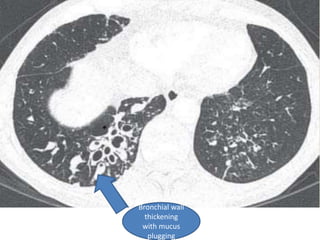

Bronchial wall

thickening

with mucus

plugging